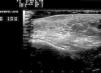

Skin ultrasound (18MHz transducer) of the nodule in the left cheek revealed a well-defined, hypoechoic dermal lesion measuring 1.37×0.24cm, with no posterior enhancement. No Doppler signal was observed and the lesion did not contain calcium deposits (Fig. 2).

Skin ultrasound can be a useful tool to confirm a diagnosis of IFAG. The typical ultrasound pattern is one of a clearly defined, solid, hypoechoic dermal lesion with no calcium deposits.1 A hyperechoic lesion with a hypoechoic center has only been observed in 2 lesions, 1 of which showed posterior enhancement.5,7 Doppler study was negative except in 2 cases.7,8 In our patient, the absence of a Doppler signal may have been related to the fact that ultrasound examination was performed during an advanced phase of the lesion, as Doppler findings in IFAG may depend on the stage of the lesion when the study is performed.